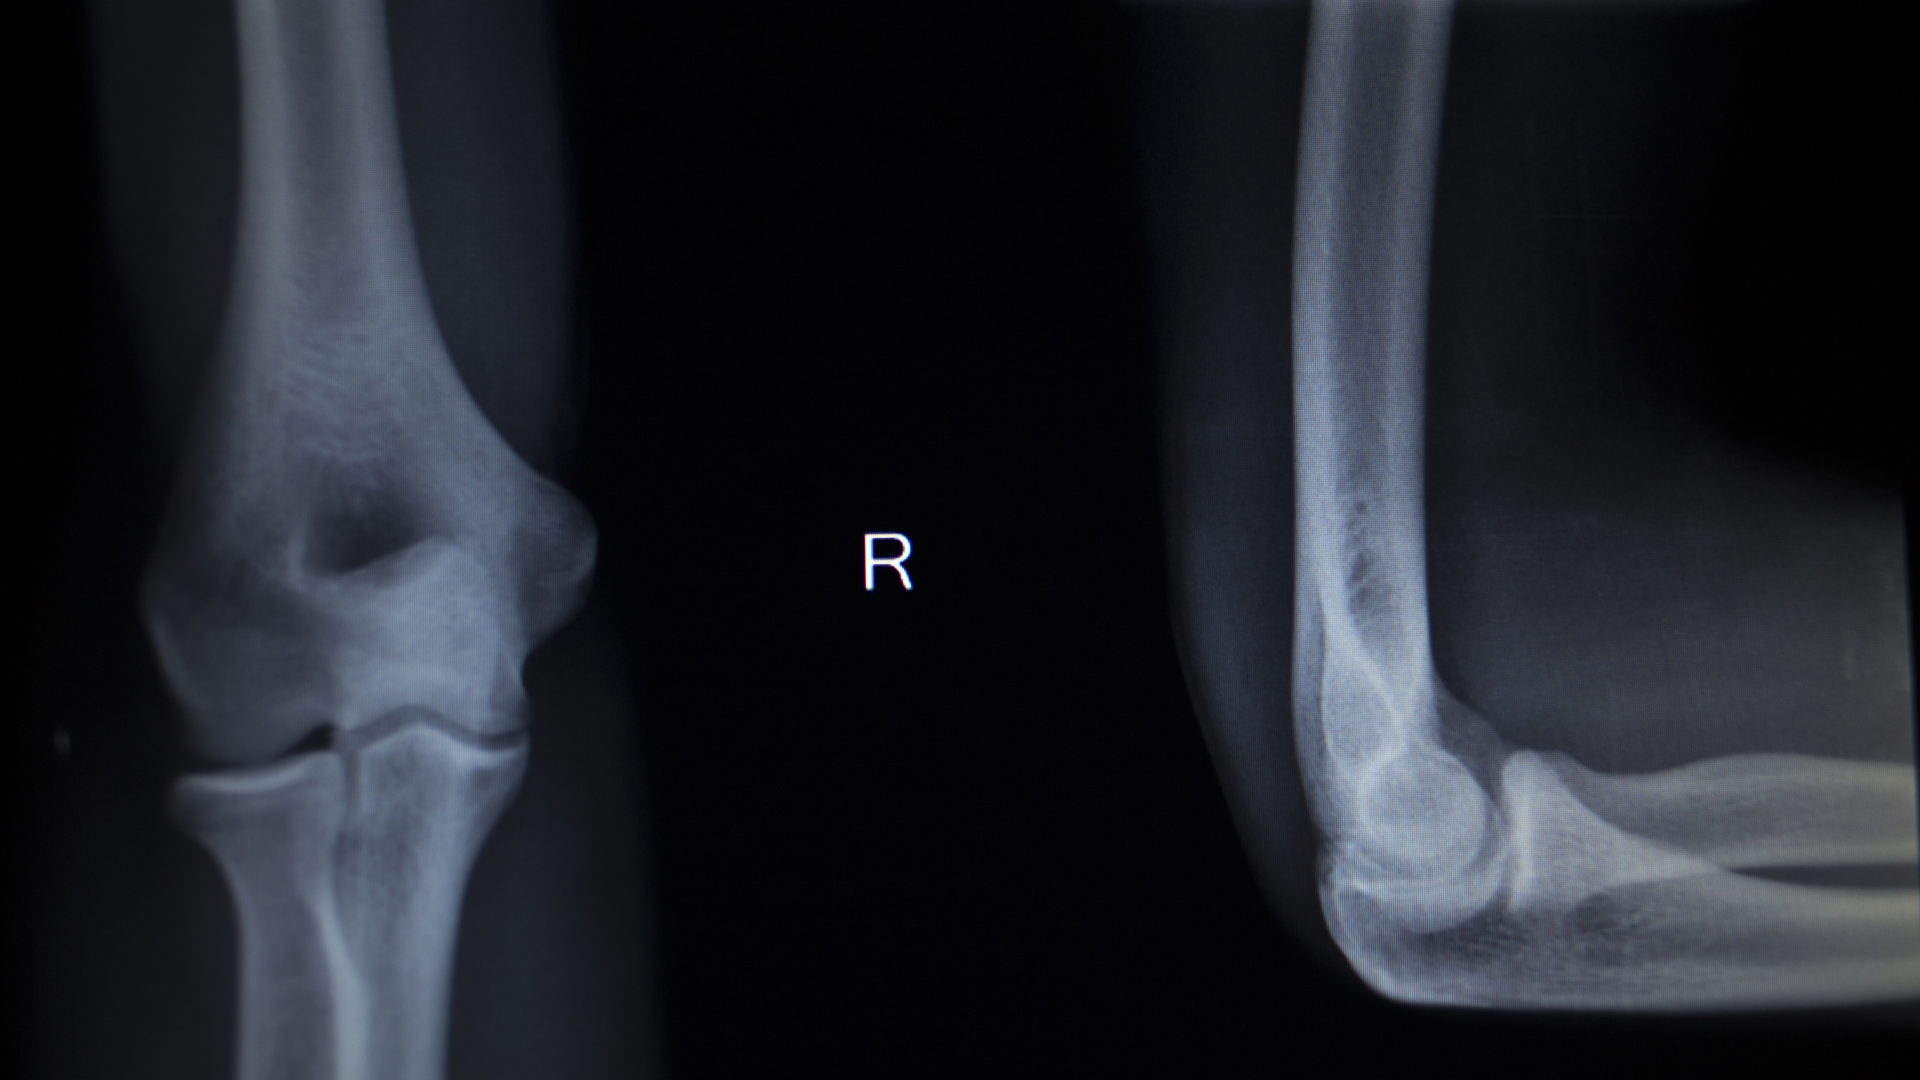

Các tư thế chụp thường gặp

Để đánh giá chính xác, kỹ thuật viên có thể yêu cầu thực hiện nhiều tư thế:

- Tư thế thẳng.

- Tư thế nghiêng.

- Tư thế chếch.

Việc thay đổi góc chụp giúp quan sát rõ hơn cấu trúc khớp và phát hiện bất thường.

Hình ảnh bình thường

Một phim X-quang khớp khuỷu bình thường thường có:

- Cấu trúc xương rõ nét.

- Khe khớp đều.

- Không có dấu hiệu lệch trục.

Dấu hiệu bất thường

Một số dấu hiệu có thể gợi ý vấn đề:

- Xuất hiện đường gãy.

- Lệch vị trí khớp.

- Hẹp khe khớp.

- Hình thành gai xương.